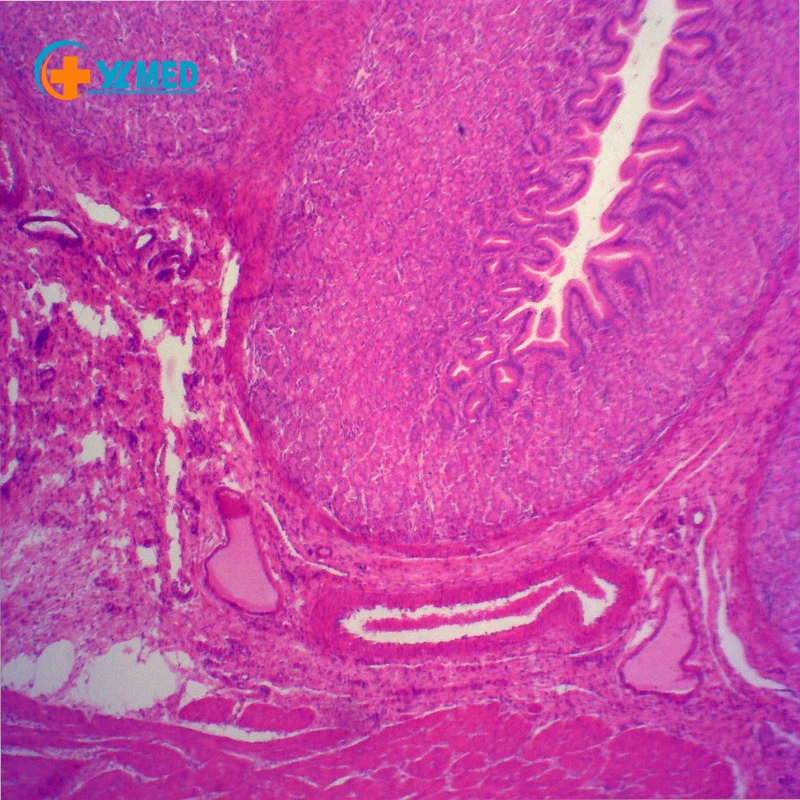

Гистология пищеварительная